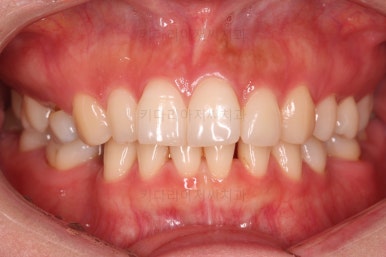

부산인비절라인 치료 시작 5개월만의 모습입니다.

일반적인 철사교정보다 인비절라인이 가지는 장점은 배열->공간폐쇄->마무리 로 단계별로 나뉘는 철사교정에 비해 이 세 단계를 동시에 진행할 수 있어서 치료기간에 이득이 되는 경우가 많다는 점인데요.

5개월만에 벌써 많은 부분이 개선되었네요.

공간폐쇄가 다 되었고, 치열도 매우 가지런해졌습니다.

첫번째 치료가 끝난 것인데요.

아직 모자란 부분들이 많습니다.

중앙선이 아직 기대에 못미치고요. 100% 공간이 정렬이 덜 되었습니다.

교합도 아직 부족하고요.